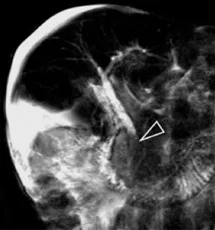

Figure 1. Patient exploré par bili-IRM pour une suspicion de migration lithiasique.

A. Cette coupe de bili-IRM 2D montre de multiples lithiases vésiculaires, ainsi qu’un calcul du bas cholédoque (tête de flèche).

B. Sur cette projection cholangiographique « MIP » issue d’une acquisition 3D en coupes fines, le calcul cholédocien est trop

petit au sein de cette VBP dilatée, et il n’est pas correctement visualisé. En cas de bili-IRM 3D, l’analyse de chacune des coupes

fines du volume est impérative. Ainsi, contrairement à la projection « MIP », la coupe fine passant par le cholédoque permet

de bien montrer le calcul (C)